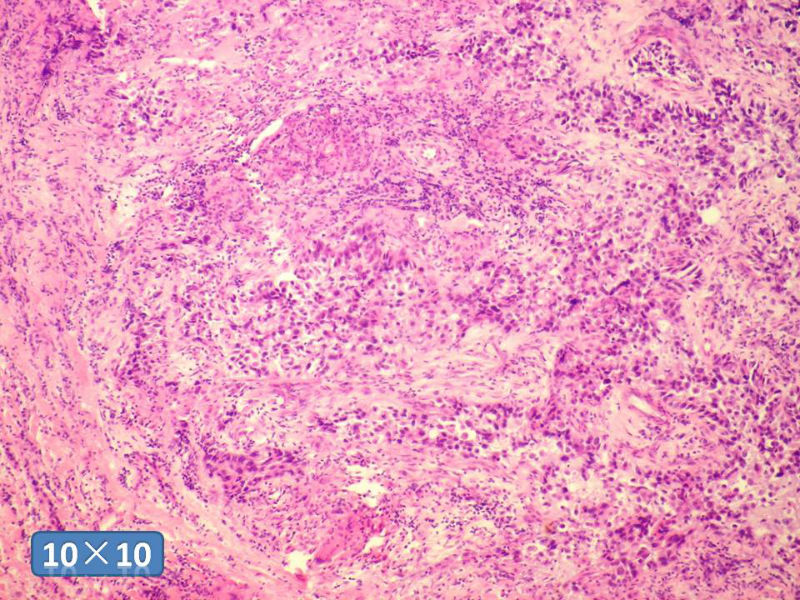

女性,50岁,乳腺肿物,冰冻切片(图1-25)

HE